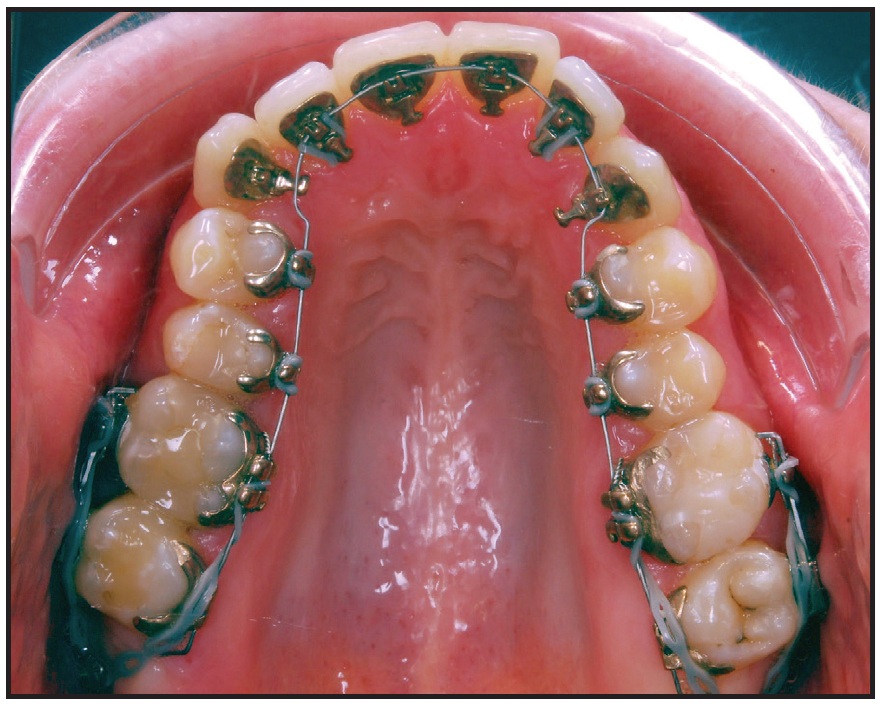

Two Dual-Top* JA standard mini-implants (1.6mm x 10mm) were placed distal to the second molars in the maxillary tuberosities (Fig. 2). One and a half months later, since the patient wanted to be treated with invisible appliances, the Incognito** lingual system was bonded and an .014" nickel titanium archwire was inserted (Fig. 3). This appliance is compatible with skeletal anchorage and has proven reliable in complex treatments. Gentle force was applied with elastic chain from the miniscrews to distalize the upper teeth. To prevent undesirable transverse movement of the molars, tubes or brackets were bonded to the buccal surfaces of the first and second molars and connected by sectional .016" x .022" nickel titanium wires.

Fig. 3 One and a half months later, Incognito** lingual bracket system bonded, .014" nickel titanium archwire inserted, and gentle forces applied with power chain from miniscrews to distalize upper teeth. Tubes or brackets bonded to buccal surfaces of first and second molars and sectional .016" × .022" nickel titanium wires placed to prevent undesirable transverse movement.

The posterior left crossbite and right edge-to-edge bite had been corrected by applying a bit more force from the lingual side, allowing expansion of the maxillary teeth to resolve the anteroposterior and transverse problems. As planned, there was a substantial amount of posterior intrusion. This changed the open bite from anterior to posterior; in other words, the divergence between the upper and lower occlusal planes had shifted to a convergence of planes. Because the distalization force was applied from the mini-implant in the tuberosity to the bracket at the crown level, distal crown tipping was inevitable. Bodily movement was achieved by passing the buccal chain over the molar tubes, creating a downward force, and by increasing the size of the lingual archwire (Fig. 4B). Incognito has an advantage in this respect because it uses a ribbon arch instead of an edgewise wire. Additionally, because the archwire has a large vertical cross-section, it compensates for the tipping effect by filling the bracket slot.